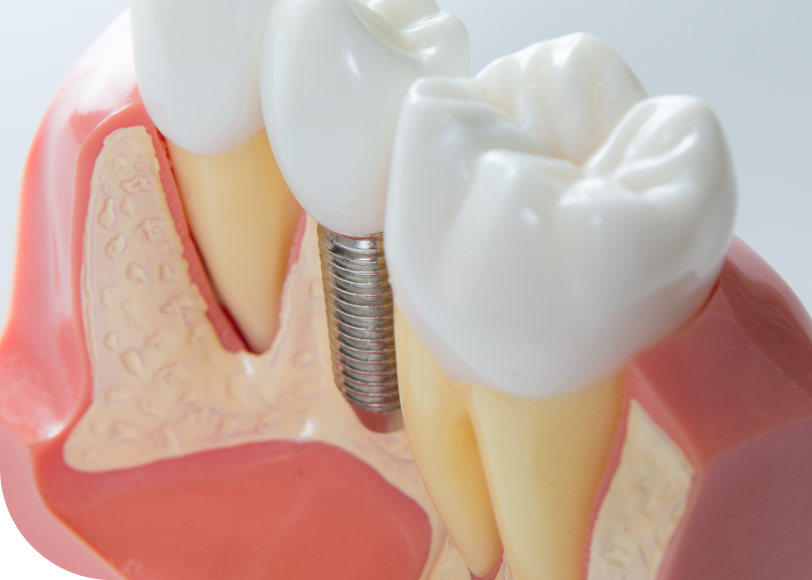

Un implant dentaire unitaire remplace une dent manquante de façon autonome. Il s’insère directement dans l’os de la mâchoire et soutient ensuite une couronne dentaire fabriquée sur mesure. Grâce à cette technique, il devient possible de restaurer efficacement la mastication tout en préservant l’alignement des autres dents.

Par ailleurs, l’implant agit comme une véritable racine artificielle. Grâce à son ancrage solide dans l’os, il soutient la couronne fixée au-dessus. De ce fait, il empêche les dents voisines de se déplacer et limite la résorption osseuse. En conséquence, le volume de la mâchoire se maintient plus longtemps, ce qui favorise une bonne stabilité fonctionnelle et esthétique.

Le jour de l’intervention, le praticien réalise une anesthésie locale. Il ouvre la gencive pour accéder à l’os. Ensuite, il insère l’implant en titane. Il le visse avec précision dans l’os alvéolaire. Puis, il referme la gencive avec quelques points de suture.

Le patient repart le jour même. Toutefois, il faut attendre entre deux et six mois pour que l’os fusionne avec l’implant. Cette phase s’appelle l’ostéo-intégration.

Étape 3 : la pose de la couronne

Une fois l’implant bien intégré, le dentiste fixe un pilier de connexion. Ensuite, il installe la couronne personnalisée. Cette dernière est conçue pour s’intégrer harmonieusement à la dentition existante.